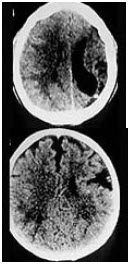

(单选题)根据CT表现,最可能的诊断是( )

A:小脑扁桃体下疝

B:脑性瘫痪

C:颅底凹陷症

D:扁平颅底

E:先天性脑积水